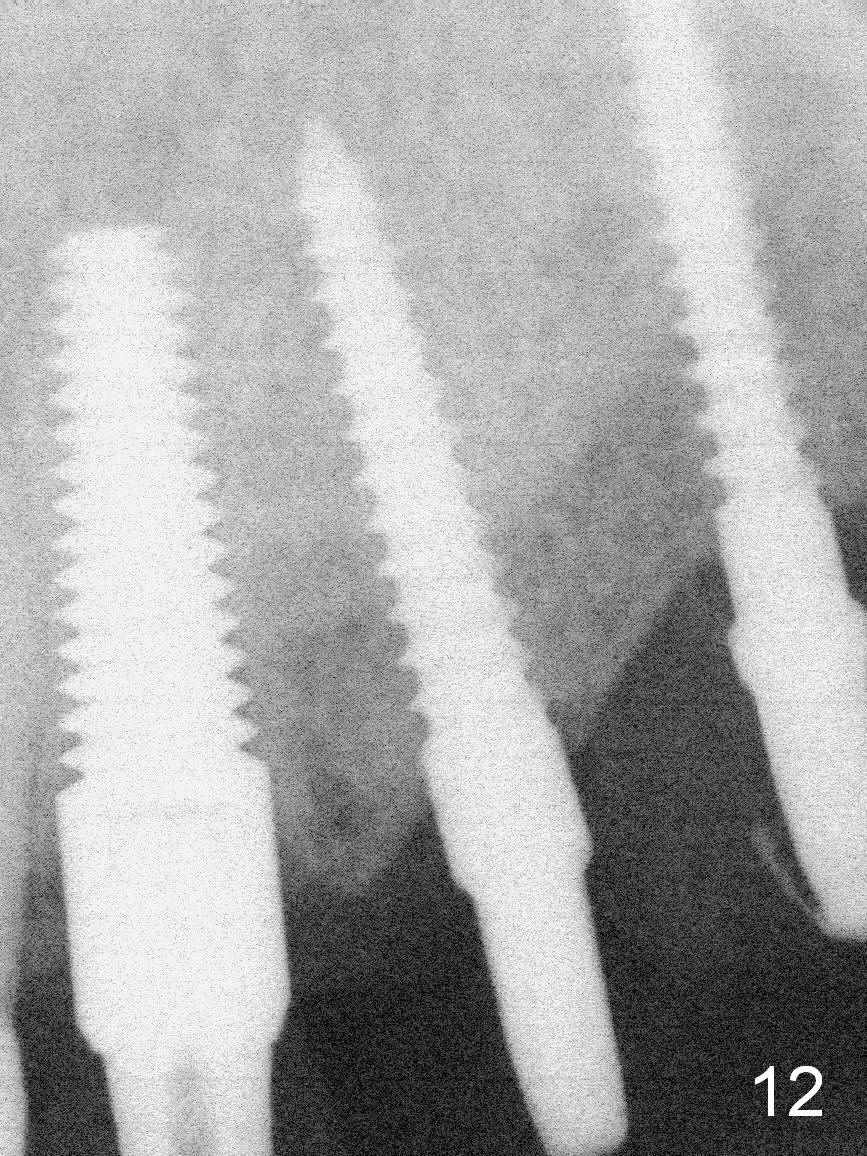

The patient returns for final restoration 3.5 months postop; it appears that the implants have osteointegrated (Fig.12,13).  After reprep, there is no gross buccal plate atrophy at #10 (Fig.14).